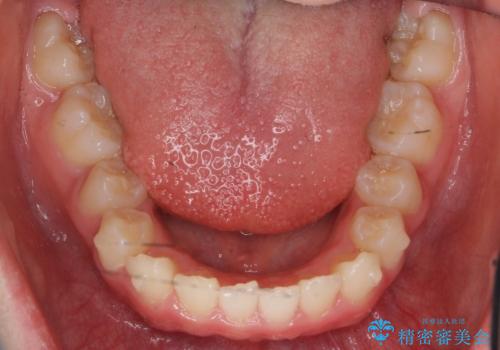

八重歯 歯を抜かずにインビザラインで

- 八重歯を主訴に来院。

抜かずに歯を少し削って入れる方法で並べました。

乳歯が永久歯に生え変わるまで成長観察を続け、永久歯列になってから治療開始しています。